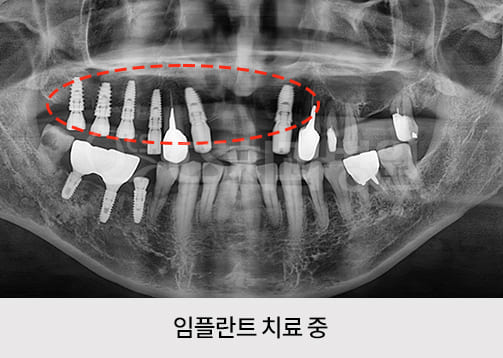

치료기간 : 2022.12.22 ~ 2023.07.27